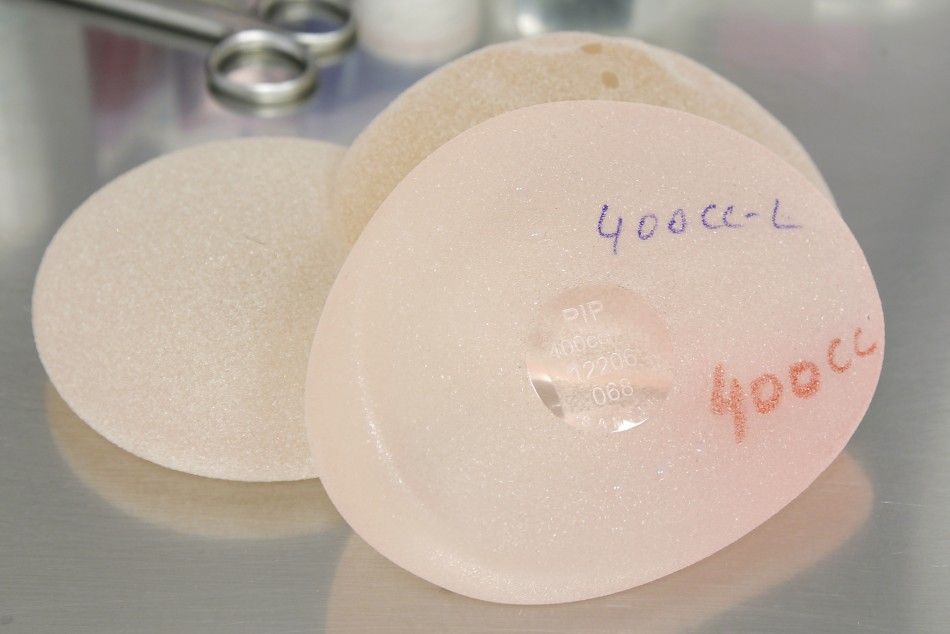

Анатомические импланты Eurosilicone

Раздел: Визуальный дайджест